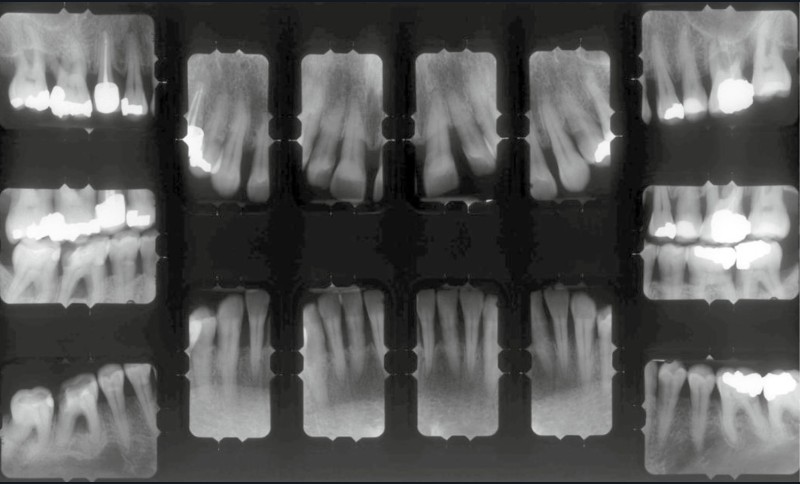

L’examen radiographique (fig. 3-5) nous indique une Classe I squelettique de Ballard (ANB 0°) sur un schéma facial à tendance hyperdivergent (FMA 28°). L’analyse céphalométrique confirme la vestibulo-version incisive (I/SN 111° ; IMPA 94°). La lyse osseuse est généralisée.